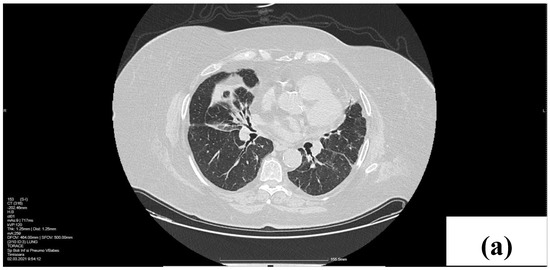

2. Case Presentation

2.1. Laboratory, Radiological, and Histological Examinations

2.2. Treatment and Outcome